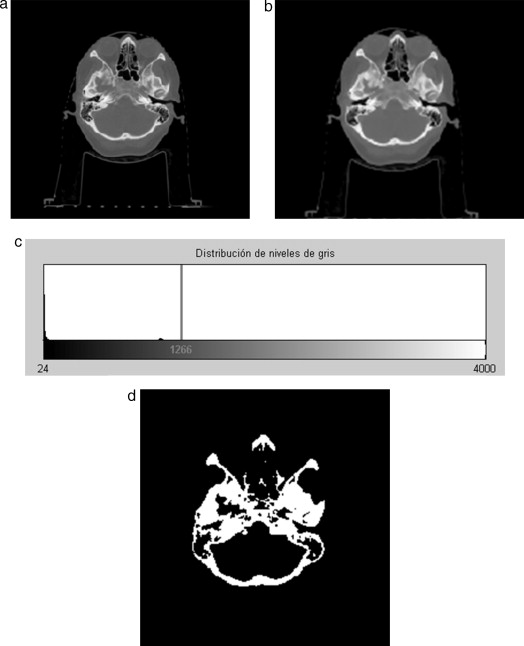

En la figura 22 se presenta la segmentación del cráneo en imágenes de TC en formato DICOM, 256 slices , tamaño de corte de 512 × 512 pixels, voxel spacing: 0,98 × 0,98 × 1,0 mm. Para obtener un valor umbral que distinga el tejido óseo de los demás tejidos, se analizó el histograma global de la imagen, donde claramente se observa que el tejido óseo posee los niveles de gris más altos. En este caso de estudio en espacial, los voxels de la imagen de entrada menores a un umbral de valor 1.266 fueron convertidos a negro, y los voxels con valores mayores al umbral fueron convertidos a blanco. De este modo, se obtuvo un volumen binario del hueso craneal.

|

|

|

Figura 22. Técnica de umbralización aplicada a TC. (a) Vista original de un corte axial de TC. (b) Imagen filtrada con difusión anisotrópica. (c) Histograma de imagen b. (d) Imagen binaria resultante de umbralizar imagen b con un umbral de 1266. |